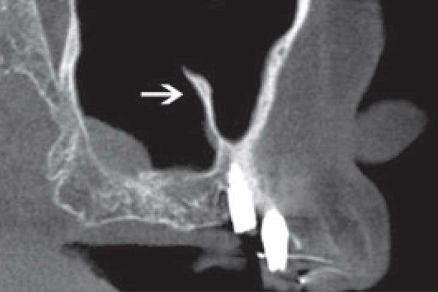

Los septos suelen ser crestas óseas puntiagudas o con forma de arco gótico (6,7,8,9) que se ubican en el seno maxilar, generalmente son hallazgos radiológicos, son de tamaño variable llegando incluso a dividir el seno completamente en dos o más cavidades (1, 2,10-13), su diagnóstico diferencial son las exostosis, sin embargo éstas tienen forma redondeada (6,7,8) (figura 1).

De acuerdo a su origen, existen dos tipos de septos: los primarios y los secundarios. Los primarios o llamados también septos congénitos, se forman durante el desarrollo de la zona central de la cara, originándose de la fusión de residuos durante la formación del seno maxilar (12), (figura 2 y 3); sin embargo Underwood relaciona su origen con las piezas dentarias justificando que se forman por separaciones intermedias del piso antral debido al desarrollo radicular (14). Autores como Lee et al., mencionan que los septos se originan por proyecciones digitales debido a la invaginación del infundíbulo etmoidal durante el desarrollo embrionario donde las paredes adyacentes no se reabsorben (2).